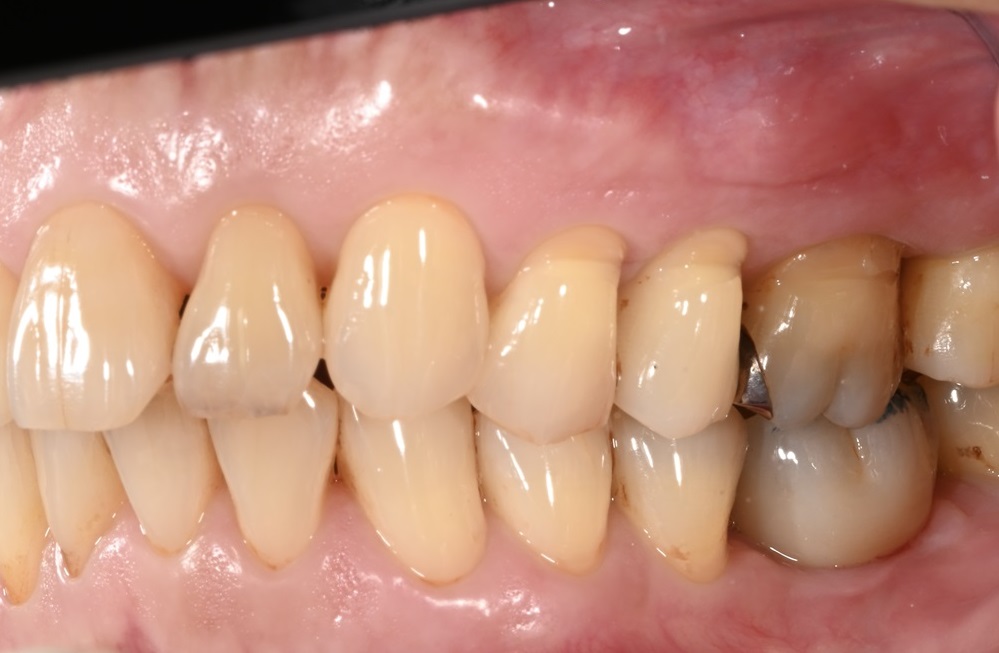

4本のインプラントですべての歯が入るAll-on-4に対応

画像

インプラントのメリットは、周りにあるほかの健康な歯には負担をかけないこと、ご自身の歯のような噛み心地を再現できることです。しかし、どうしても費用の負担が大きくなってしまいます。

失った歯の本数だけインプラントを入れようとすると、負担に感じる方が多いのではないでしょうか。そこで行っているのがAll-on-4(オールオンフォー)です。片顎につき最小4本のインプラントですべての歯を支えることができます